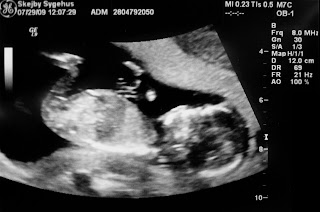

Her er seneste skud på stammen her hos os i Søften! Den fineste lille baby, med bøjede ben, lidt genert (den vender hovedet væk) og hænder der danser ovenover maven. Spørg lige om vi glæder os til slutningen af januar 2010….. DET GØR VI!!! Der bliver Ole storebror til en lillesøster 🙂